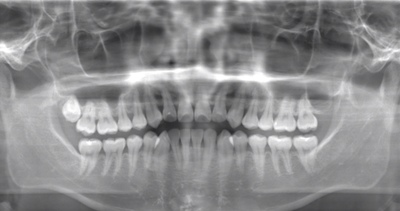

CASE 2

| 年齢・性別 | 30代・男性 |

| 主訴 | 左上下親知らず抜きたい |

| 抜歯期間 | 30分 |

| 抜歯費用 | 約2,500円(保険内) 別途CT撮影で3,000円 |

| 抜歯内容 | 左上下の親知らず抜歯 |